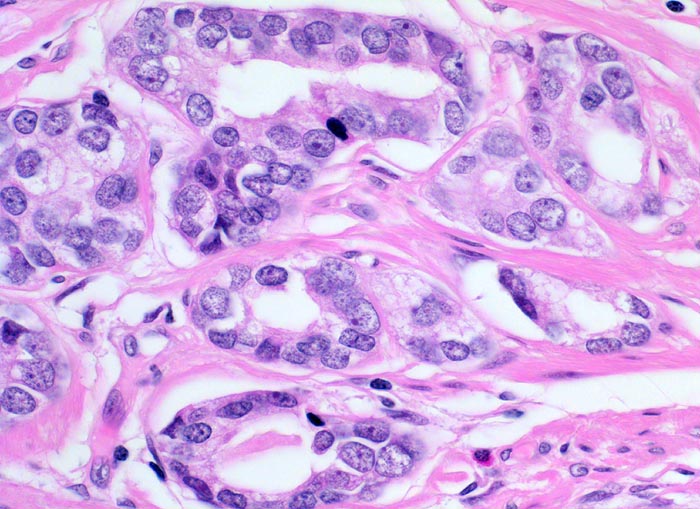

Adenokarzinom der Prostata

Mittelgrosse, gut geformte Karzinomdrüsen ausgekleidet durch ein einreihiges kubisches Epithel ohne Basalzellschicht. Die einzelnen Drüsen sind voneinander durch wenig Stroma getrennt. Die Karzinomzellen haben deutlich vergrösserte hyperchromatische Kerne mit deutlich erkennbaren, aber nicht sehr grossen Nukleolen.

Histologie

400